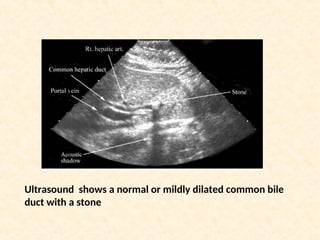

Ultrasound shows a normal or mildly dilated common bile

duct with a stone

Ultrasound shows anormal or mildly dilated common bile duct with a stone